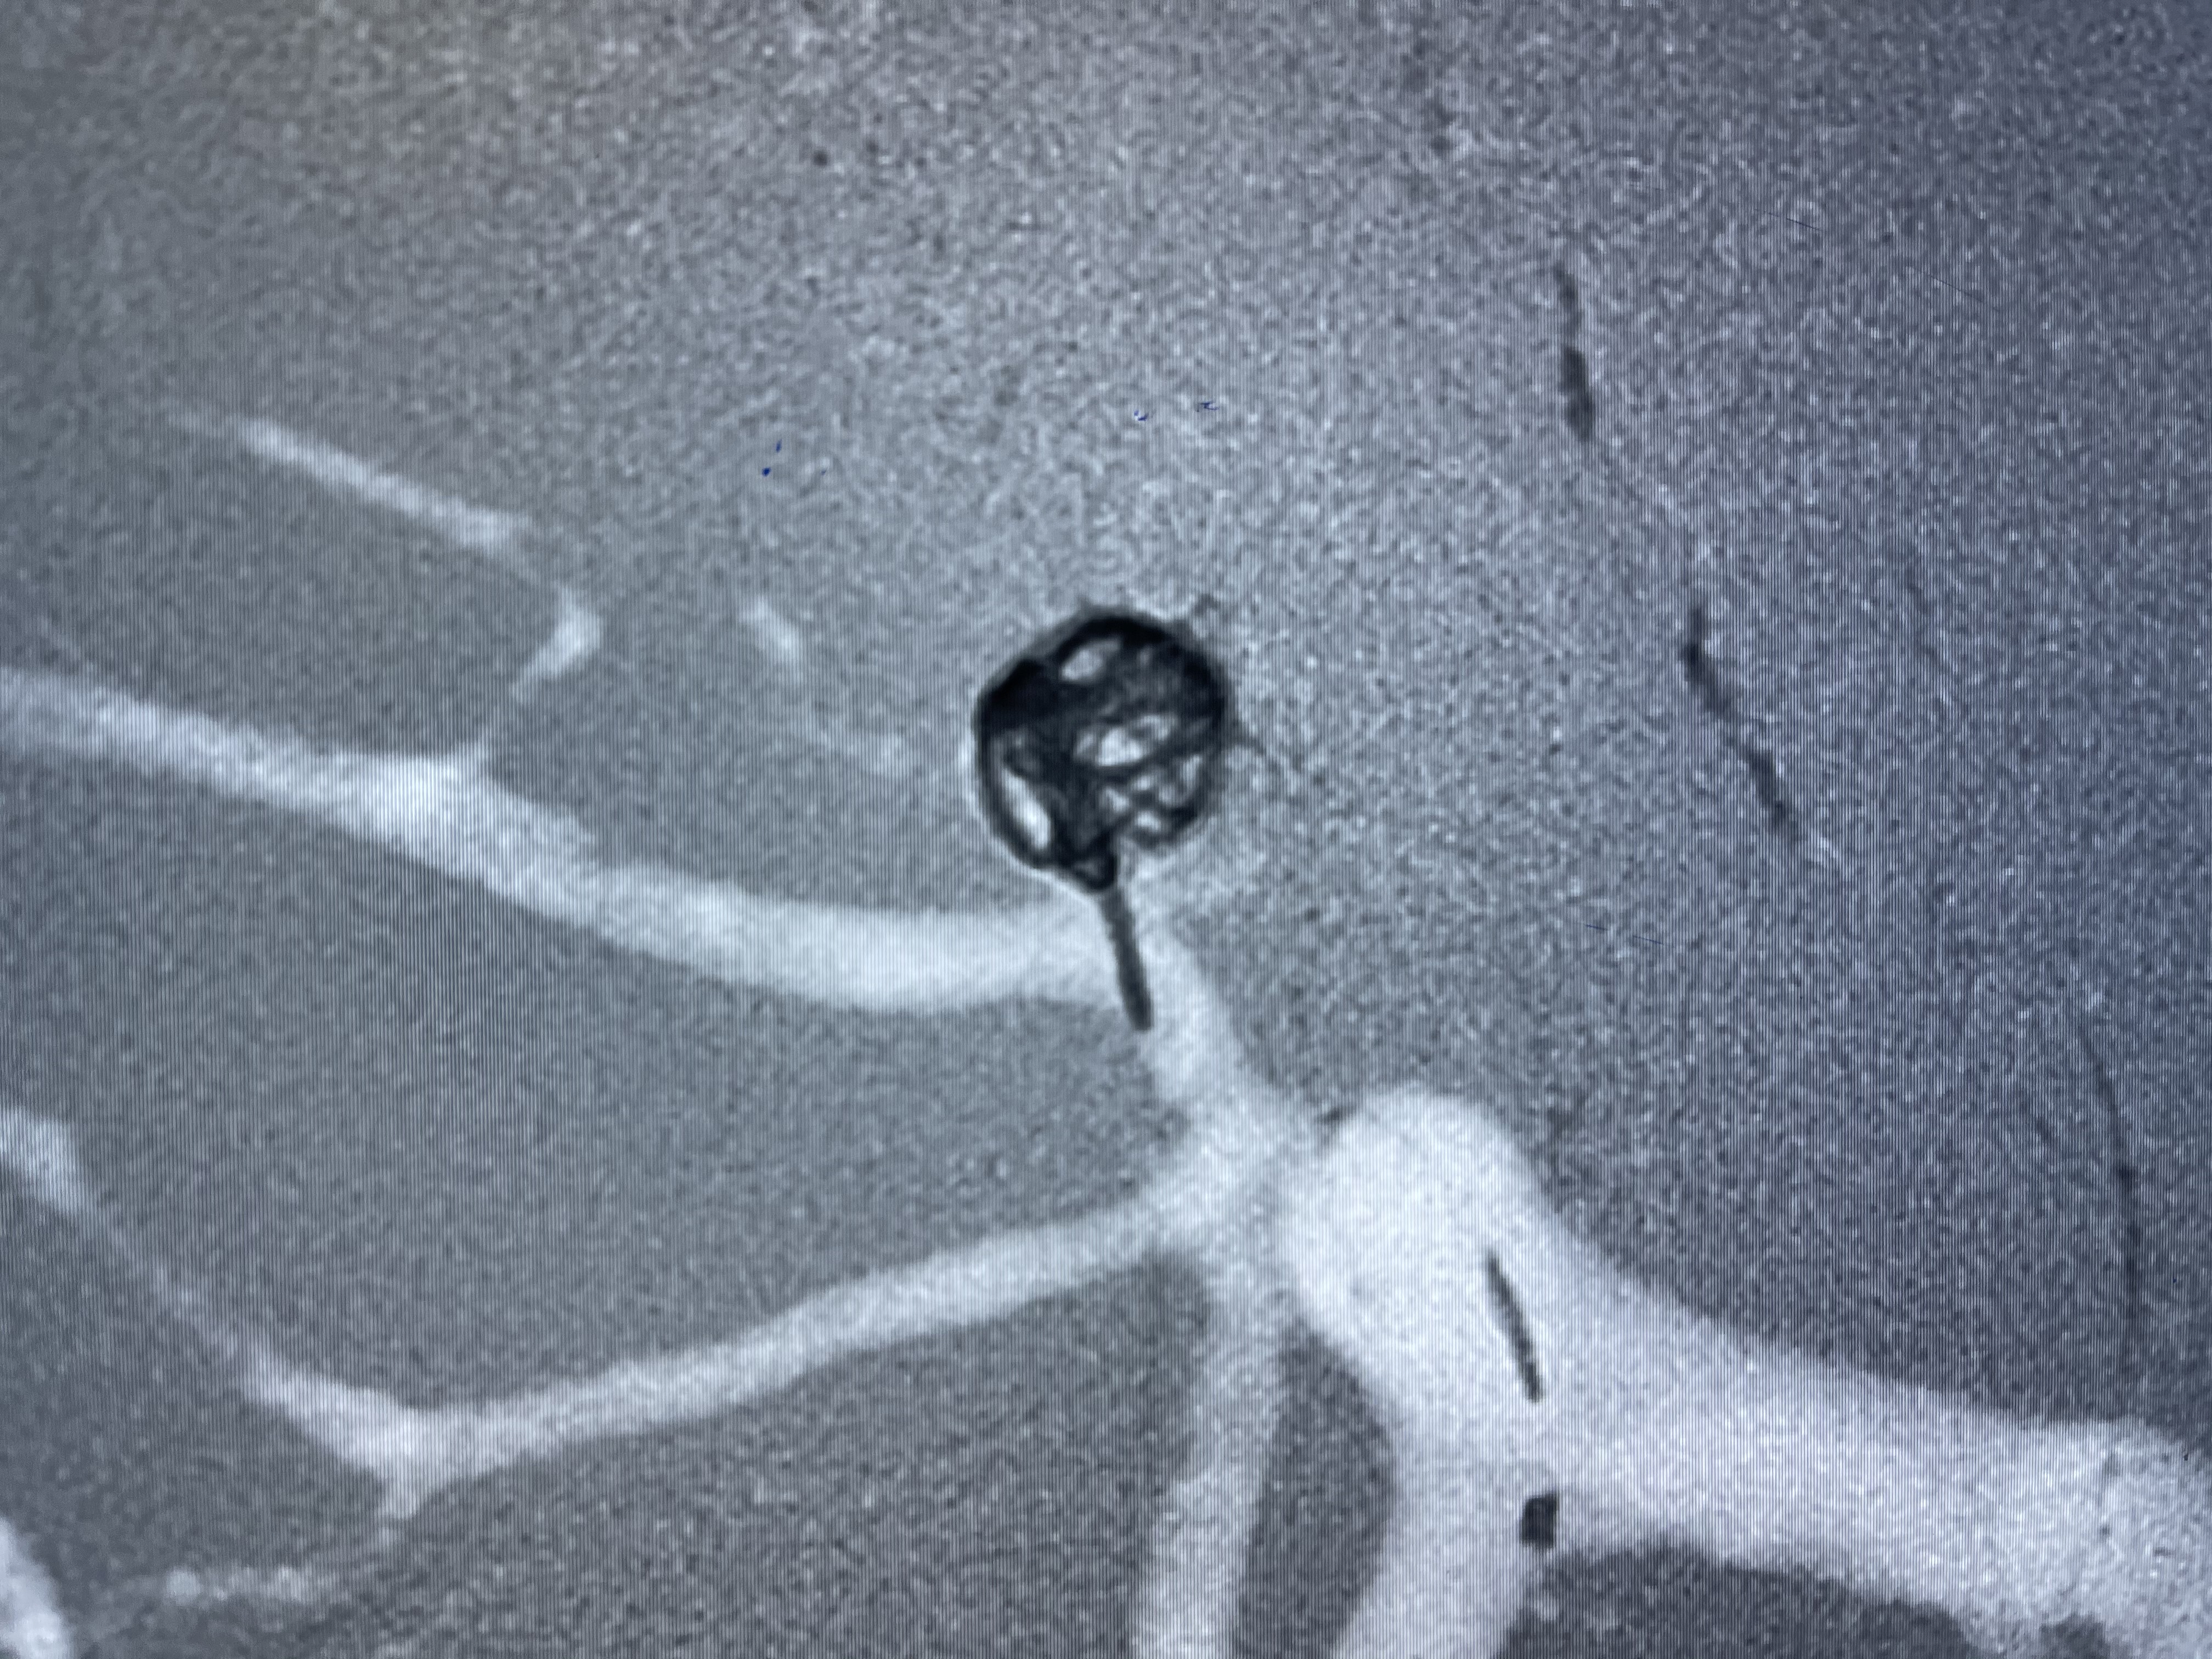

2021-01-11全麻下双微导管栓塞

工作角度显示瘤颈

E10 45°角微导管塑形后轻松到位

5-15cm三维圈成篮:瘤颈部覆盖弹簧圈